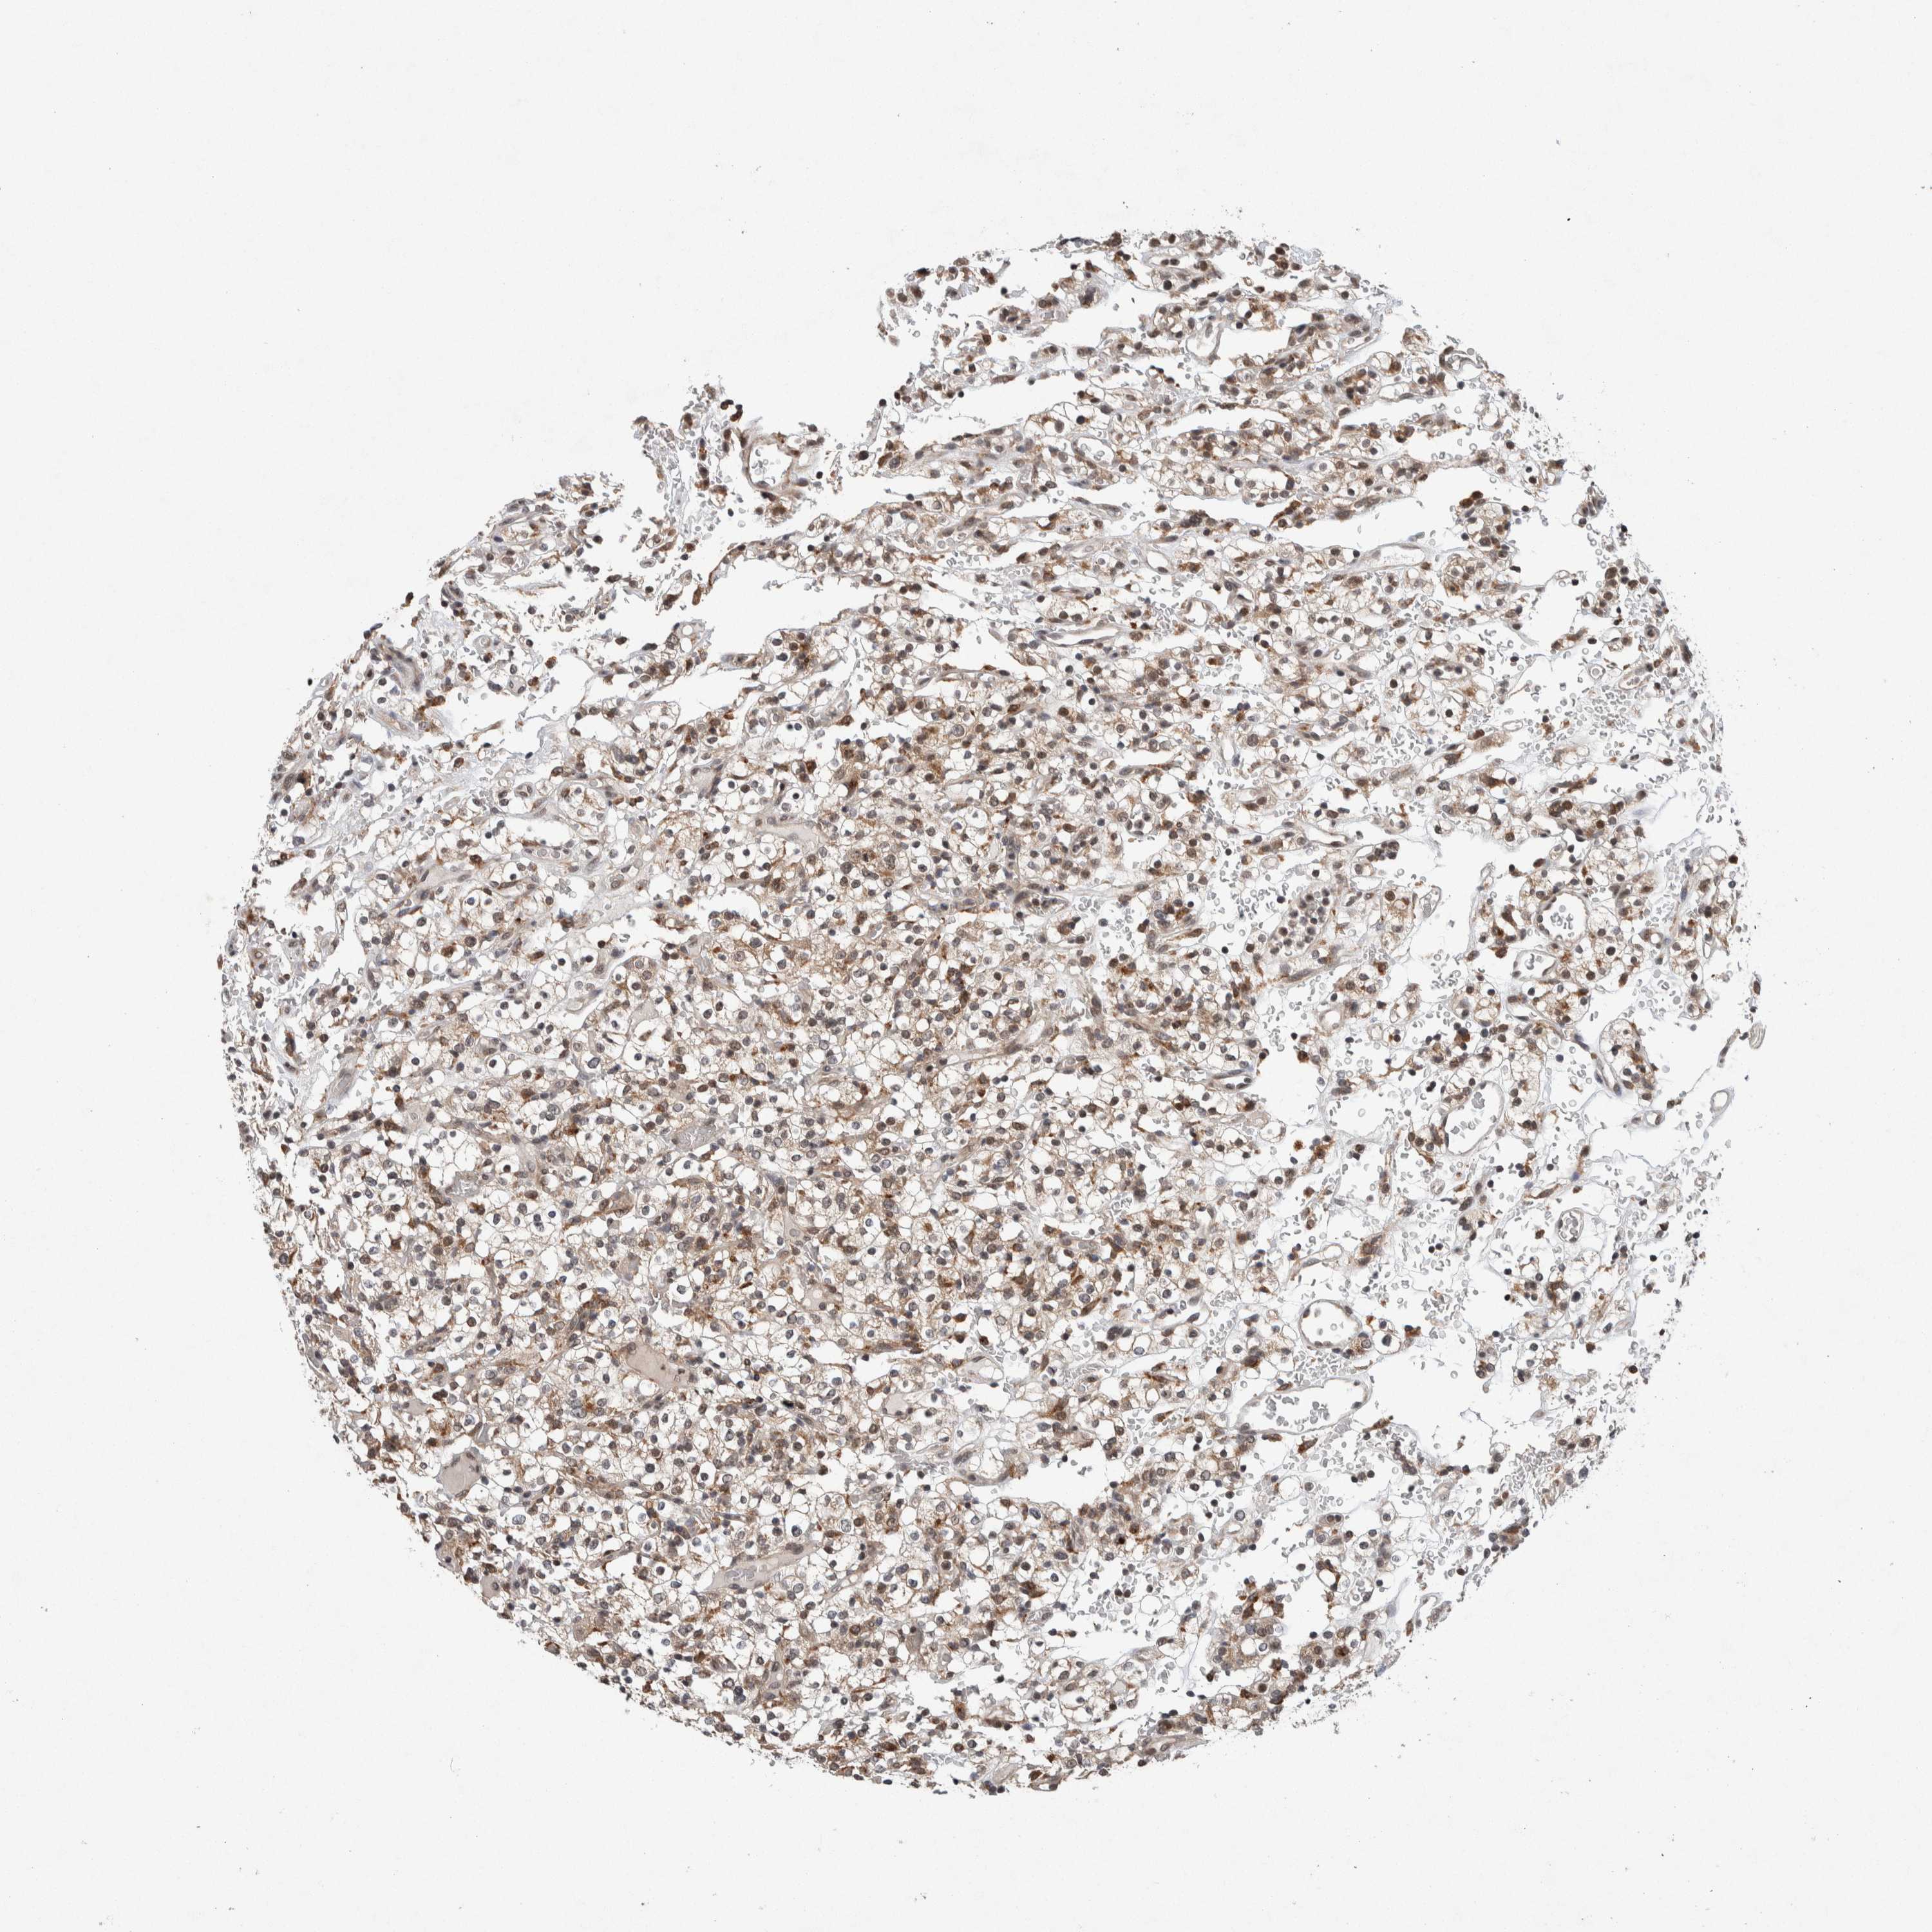

KIDNEY RENAL CLEAR CELL CARCINOMA (TCGA) - Interactive survival scatter ploti

The Survival Scatter plot shows the clinical status (i.e. dead or alive) for all individuals in the patient cohort, based on the same data that underlies the corresponding Kaplan-Meier plots. Patients that are alive at last time for follow-up are shown in blue and patients who have died during the study are shown in red.

The x-axis shows the expression levels (FPKM) of the investigated gene in the tumor tissue at the time of diagnosis. The y-axis shows the follow-up time after diagnosis (years). Both axes are complimented with kernel density curves demonstrating the data density over the axes. The top density plot shows the expression levels (FPKM) distribution among dead (red) and alive patients (blue). The right density plot shows the data density of the survived years of dead patients with high and low expression levels respectively, stratified using the cutoff indicated by the vertical dashed line through the Survival Scatter plot. This cutoff is automatically defined based on the FPKM cutoff that minimizes the p-score. The cutoff can be changed by dragging the vertical line or by entering a cutoff value in the square labeled "Current cut-off".

Under the Survival Scatter plot the p-score landscape (black curve; left axis) is shown together with dead median separation (red curve; right axis). Dead median separation is the difference in median mRNA expression between patients who have died with high and low expression, respectively. It is calculated as follows: median FPKM expression of dead patients with high expression - median FPKM expression of dead patients with low expression. This is intended to aid the user in visually exploring custom cutoffs and the associated p-scores and dead median separation.

Individual patient data is displayed and can be filtered by clicking on one or more of the category buttons on the top of the page. Categories describing expression level and patient information include: high, low, alive, dead, female, male and tumor stages. The scale of the x-axis can be toggled between linear and log-scale by clicking on the "x log" button. Mouse-over function shows TCGA ID, patient information and mRNA expression (FPKM) for each patient.

& Survival analysisi

Kaplan-Meier plots summarize results from analysis of correlation between mRNA expression level and patient survival. Patients were divided based on level of expression into one of the two groups "low" (under cut off) or "high" (over cut off). X-axis shows time for survival (years) and y-axis shows the probability of survival, where 1.0 corresponds to 100 percent.

KCNK1 is not prognostic in Kidney Renal Clear Cell Carcinoma (TCGA)

Best expression cut offi

Based on the FPKM value of each gene, patients were classified into two groups and association between prognosis (survival) and gene expression (FPKM) was examined. The best expression cut-off refers the FPKM value that yields maximal difference with regard to survival between the two groups at the lowest log-rank P-value. Best expression cut-off was selected based on survival analysis .

When clicking on this number, the vertical dashed line indicating cut-off, the interactive survival plot, and the Kaplan-Meier curve will be adjusted to show results based on the best expression cut-off.

: 10.98

P scorei

Log-rank P value for Kaplan-Meier plot showing results from analysis of correlation between mRNA expression level and patient survival.

N/A

TCGA RNA samplesi

RNA-seq data is reported as average FPKM (number Fragments Per Kilobase of exon per Million reads), generated by the The Cancer Genome Atlas (TCGA) .

Normal distribution across the dataset is visualized with box plots, shown as median and 25th and 75th percentiles. Points are displayed as outliers if they are above or below 1.5 times the interquartile range. FPKM values of the individual samples are presented next to the box plot.

Average pTPM 14.0

Number of samples 521